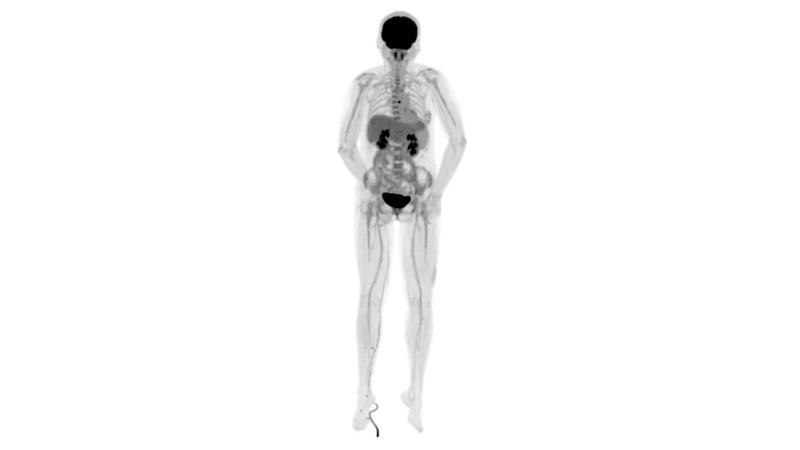

圖例

直腸癌

男,45歲,直腸癌術(shù)后9個月,發(fā)現(xiàn)肺占位

臨床診斷:直腸區(qū)術(shù)后改變,復(fù)發(fā)伴骶骨受累,雙肺多發(fā)轉(zhuǎn)移